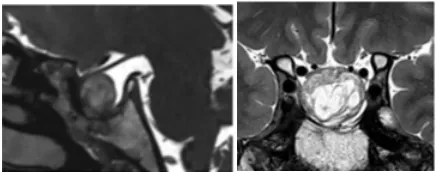

术后一年,MRI显示肿瘤全切、脂肪填充空蝶鞍(图4)。术后左侧视野好转,视力稳定在0.3,右侧视力从0.03好转到1.0、如正常视力。

图4:术后一年MRI